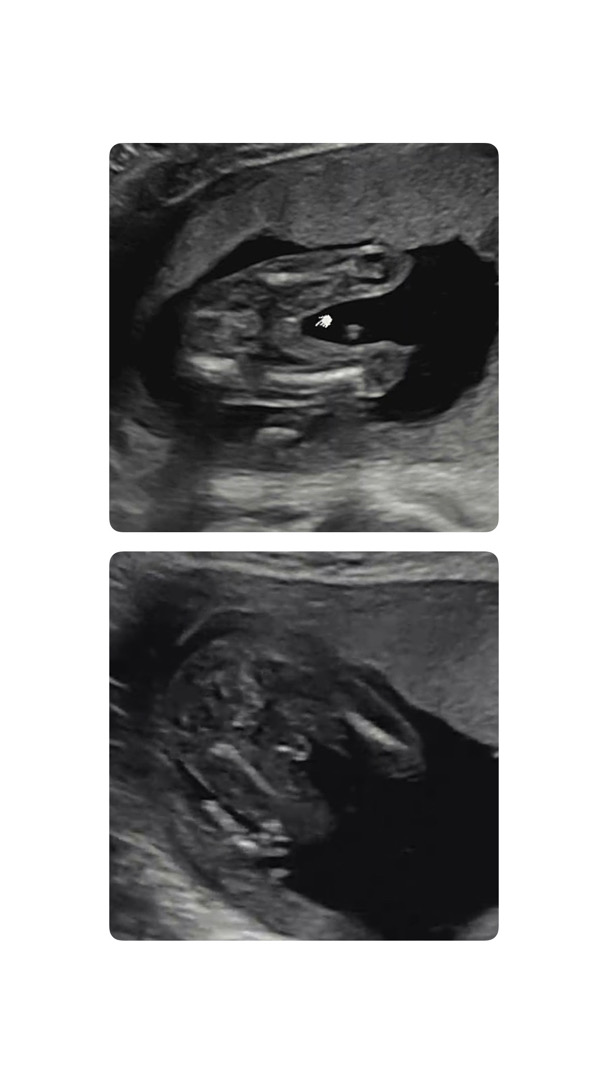

밑에 사진보명 완전 아들이네여!! 위에 사진은,, 각도가 다른걸까여? 없는게 보일리는 없으니,,,

성별이 과연 뭘까요~~ 어때 보이시나요?

같은날 본 초음파예요.. 신기하게도 이렇게 여아같기도 남아같기도 해요ㅠ

보이는 각도 별로 보였다 안 보였다해요!! 아궁